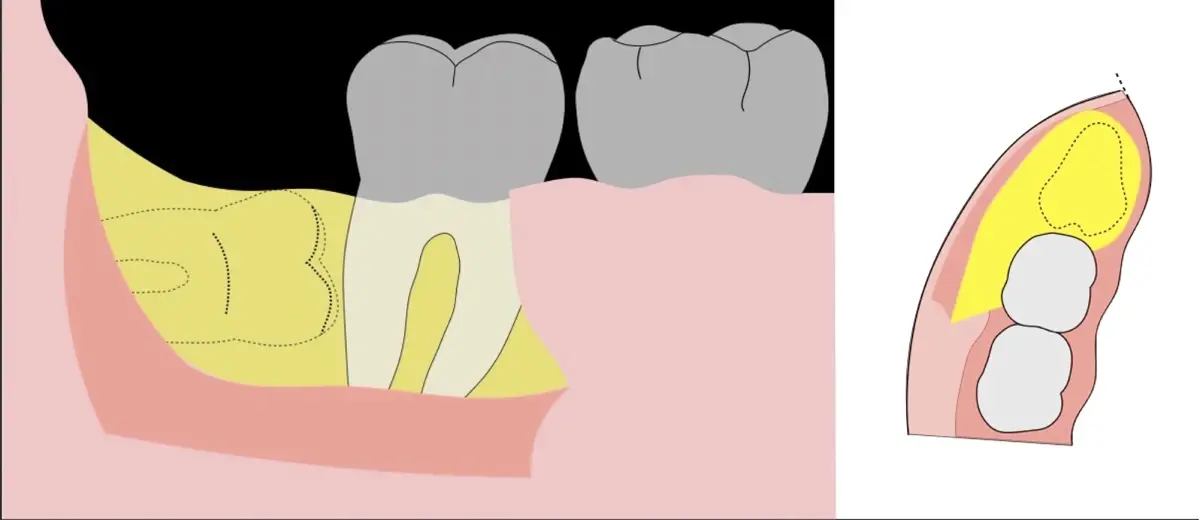

Figura 8. Odontosección mediante fresa de alta rotación y/o inserto de corte de piezoeléctrico. Posteriormente se procede al ensanchamiento del espacio pericoronario con el periótomo de piezoeléctrico para facilitar la avulsión de la pieza dentaria.

Figura 9. Avulsión de la parte coronaria de la tercera molar.

Figura 10. Tracción mesial del remanente dentario utilizando botadores en bandera.

Figura 11. Avulsión del remanente radicular de la tercera molar.